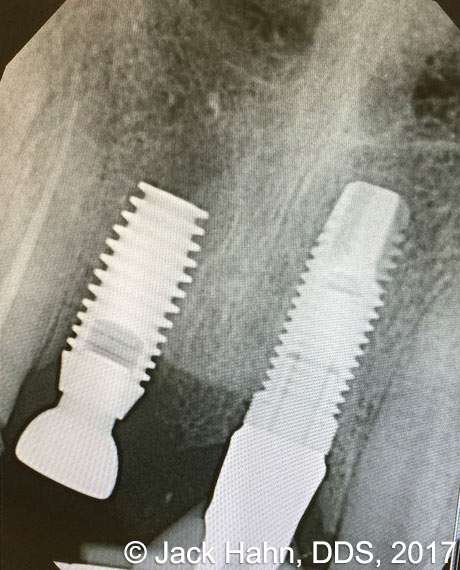

CASE #4 Trauma Case – Central Incisors Internal / External Resorption

Implants, that replace failed endo- or perio-compromised teeth, have a MUCH higher success rate with laser decontamination of the osteotomy site. LightScalpel laser surgical and perio laser tips ensure excellent access to extraction socket for the optimum removal of granulation tissue and socket decontamination (protocol involves manual curettage of the socket with alternating rinsing and lasing).

The patient, a 17-year-old female was involved in a water slide accident 3 years ago. As a result, both central incisors were avulsed and an endodontist replanted them. Both teeth exhibited internal and external resorption. Dr. Hahn extracted both central incisors, removed all the root fragments and sanitized the sites with the LightScalpel laser which also eliminated any granulation tissue. The #8 area was prepared to place a Hahn 4.3×13 Implant and #9 was prepared for a Hahn 3.5×13. 3mm tall Hahn healing abuts were placed slightly below the gingival-tissue level to help develop an emergence profile when at the restoration time in 4 months. Upon seeing the x-ray, Dr. Hahn tightened the healing abutment on #9 to be sure that it was completely seated on the implant. 45nucm. stability was achieved on both implants. He then placed some bone putty to seal any openings. To be on the safe side, he decided to place a temporary partial instead of immediate temporary prosthetics.